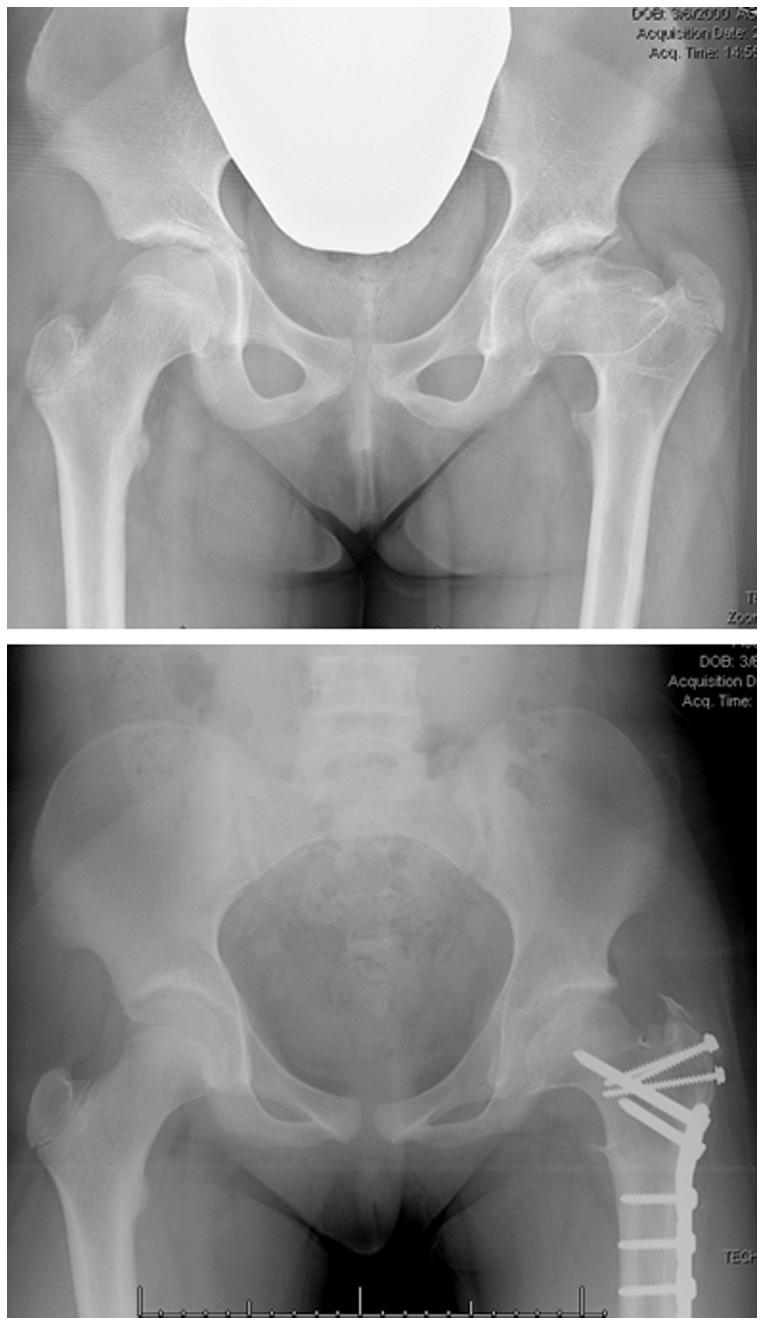

An evolution in conceptual understanding, coupled with technical innovations, has enabled hip preservation surgeons to address complex pathomorphologies about the hip joint to reduce pain, optimize function, and potentially increase the longevity of the native hip joint. Technical aspects of hip preservation surgeries are diverse and range from isolated arthroscopic or open procedures to hybrid procedures that combine the advantages of arthroscopy with open surgical dislocation, pelvic and/or proximal femoral osteotomy, and biologic treatments for cartilage restoration.

概念理解的演变与技术创新相结合,使髋关节保留外科医生能够处理髋关节的复杂病理形态,以减轻疼痛、优化功能,并有可能延长天然髋关节的使用寿命。髋关节保留手术的技术方面多种多样,从单纯的关节镜手术或开放手术到结合关节镜优势与开放手术脱位、骨盆和/或股骨近端截骨以及软骨修复生物治疗的混合手术。